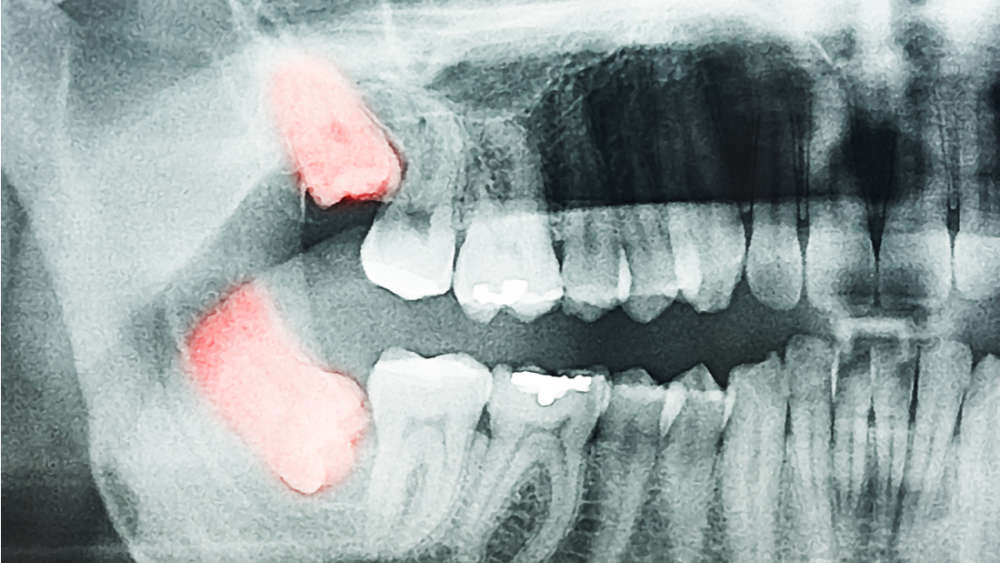

5. Недостаток на умници

Растењето на умниците може да биде навистина проблематично, но околу 40% од Азијците, 10-25% од Европејците и 11% од Афроамериканците немаат барем по еден умник. Се верува дека како и сите цицачи, така и предците на човекот имале 4 умници кои им помагале во џвакањето. Но, кога бил откриен огнот и кога храната станал помека, се намалила и вилицата. Ова го отстранило просторот кој бил наменет за умниците. Најстариот фосил без умници е од Кина и е стар околу 350.000 години.